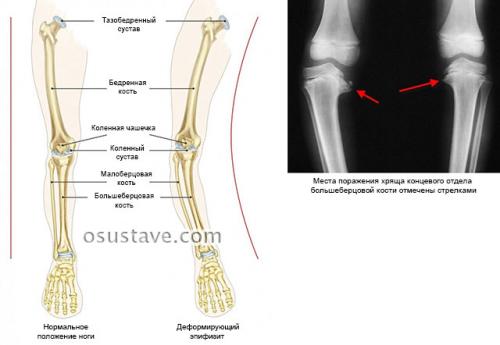

Вальгусная деформация коленных суставов – искривление ног внутрь, из-за чего они принимают форму в виде буквы «Х».

Нажмите на фото для увеличения

Подобное искривление ног (одной или двух) возникает вследствие патологических изменений в организме (разрежение, истончение костной ткани, разрушение хряща, лишний вес).

Под влиянием этих факторов колено деформируется.

В результате возникает изменение суставного пространства:

Таким образом, колени искривляются внутрь (по направлению друг к другу), а ноги образуют открытый угол (угол открыт наружу) в наружную сторону.